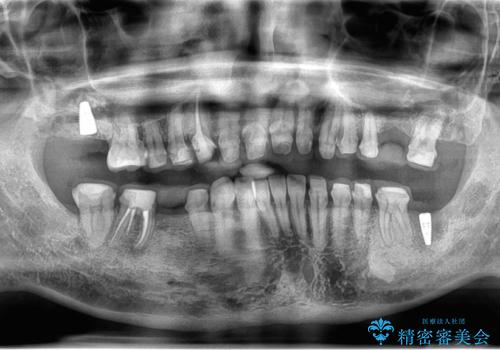

- 口の中をマスク生活の間に全て治したい、見た目を良くしたいとの事で来院。

まず徹底的に虫歯を取り除き、保存が出来ない部位は抜歯(親知らずを含む)を行い、根管治療が必要な部位は精密根管治療を行いました。

その後、インプラント治療、セラミック治療を行いました。

一度治療するはを全て仮歯に変えて、歯茎を整えてからセラミックを装着しました。

また、虫歯が歯肉の中まである場合はAPF(歯肉弁根尖側移動術)も行なっています。